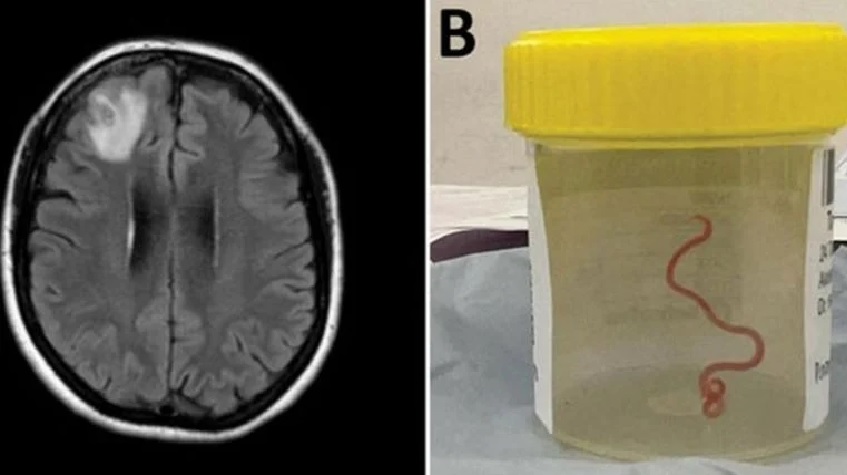

En un caso nunca antes documentado en el mundo, científicos informaron que encontraron un gusano vivo de 8 cm en el cerebro de una mujer en Australia.

La "estructura en forma de cuerda" fue extraída del lóbulo frontal lesionado de la paciente durante una cirugía en Canberra el año pasado.

Los médicos dijeron que el parásito rojo pudo haber estado vivo en el cerebro de la mujer hasta por dos meses.

Se cree que éste es el primer caso que se documenta sobre invasión y desarrollo de larvas en el cerebro humano, informaron los investigadores en un estudio en la revista Emerging Infectious Diseases (Enfermedades Infecciosas Emergentes).

EL NEMATODO EXTRAÍDO DEL CEREBRO DE UNA MUJER.

"Todos en ese quirófano sufrieron el shock de su vida cuando [la cirujana] tomó unas pinzas para detectar una anormalidad y la anormalidad resultó ser un gusano vivo, de color rojo claro, de 8 cm, que se retorcía", dijo la doctora Sanjaya Senanayake, especialista en enfermedades infecciosas del Hospital de Canberra.

UN ESCÁNER CEREBRAL Y EL NEMATODO EXTRAÍDO EN UN FRASCO DE MUESTRAS,